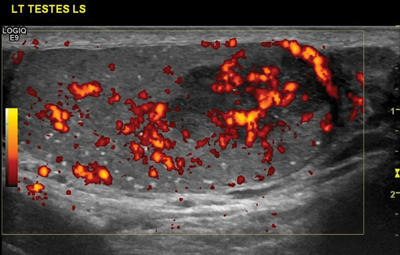

Figure 4: Same patient as Figure 3 showing a tumour in a patient

with bilateral microlithiasis. In this case, follow-up US is advised.